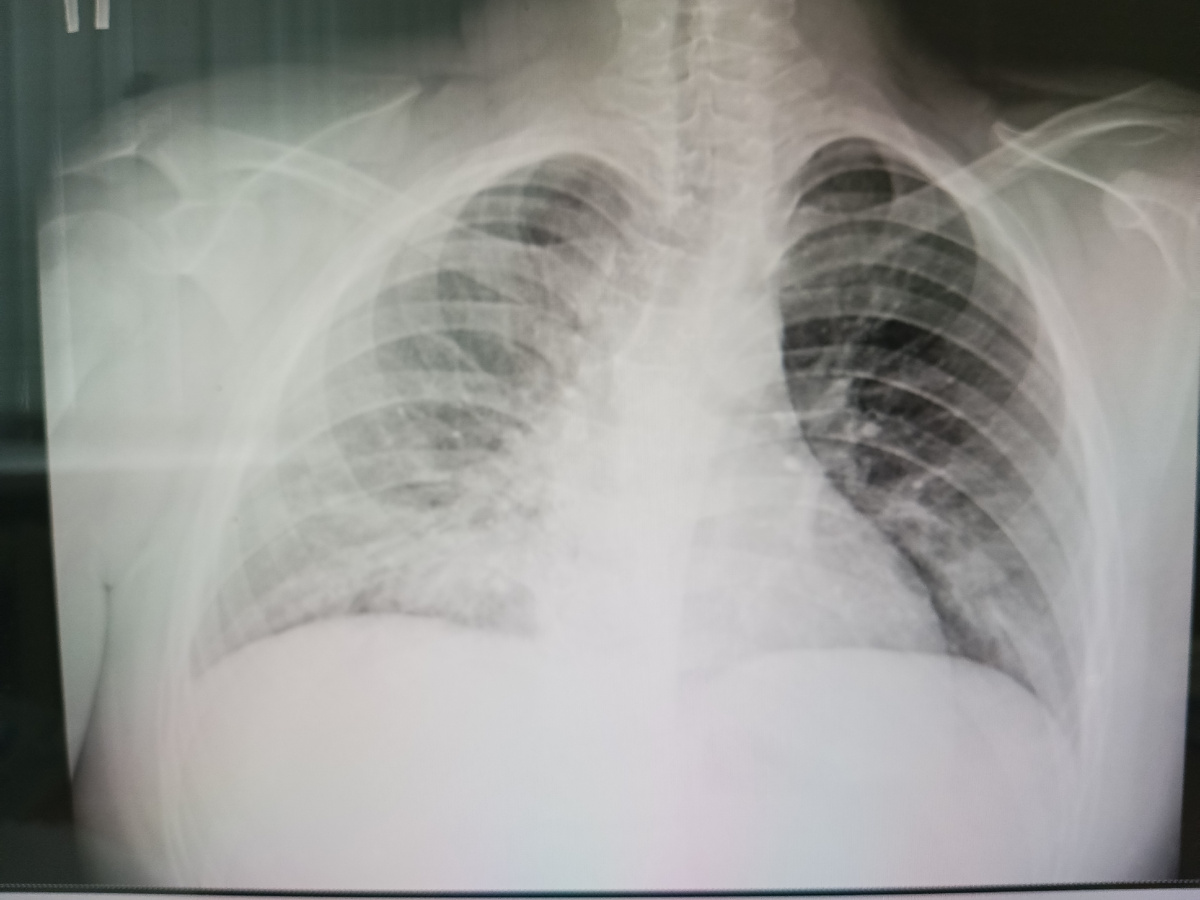

Мне бы поставить литическую смесь, взять с них отказ от госпитализации, да отправить на все четыре стороны и спать себе спокойно. Но я же не буду спокойно спать, я себя знаю. Вызываю из дома рентген лаборанта. Снимок мне в выходные никто не опишет, будем смотреть сами глазами. Увиденное подтверждает услышанное. Очагов поражения легочной ткани настолько много, что неудивительно почему такая лихорадка. Местами задействованы несколько сегментов, поражение двустороннее. Созваниваюсь с коллегами из "большого города", стационара третьего уровня.

Тоже самой пришлось выслушать вторым дублем и доказывать повторно. От транспортировки бригадой скорой медицинской помощи родители отказались. "Доедем сами". Я услышала. Но у меня все таки получилось внушить им, что ехать нужно именно сегодня. За два дня неизвестно еще что может случиться. А состояние пациента ухудшалось с каждым часом. Кроме выявленной двусторонней превмонии, присоединился так же двусторонний плеврит, гидроторакс. Выпот в плевральных полостях достигал 450 и 320 мл. Это сказалось на оксигенации крови. Ситуация упала до 73%. Ребенок был переведён в реанимационное отделение как раз той самой больницы, в которую я изначально звонила. В течение всего заболевания лихорадка продолжалась больше 18 суток. Ребёнок на кислородной зависимости. Усугубляло ситуацию и сопутствующая патология. Шла смена антибактериальной терапии с одного на другой. Комбинация препаратов. Решением врачебной комиссии пациенту назначались препараты, запрещенные в детской практике (по жизненным показаниям их назначают в исключительных случаях). Конечно же, добавились грибковые осложнения. Все это говорило о тяжелом течении пневмонии.